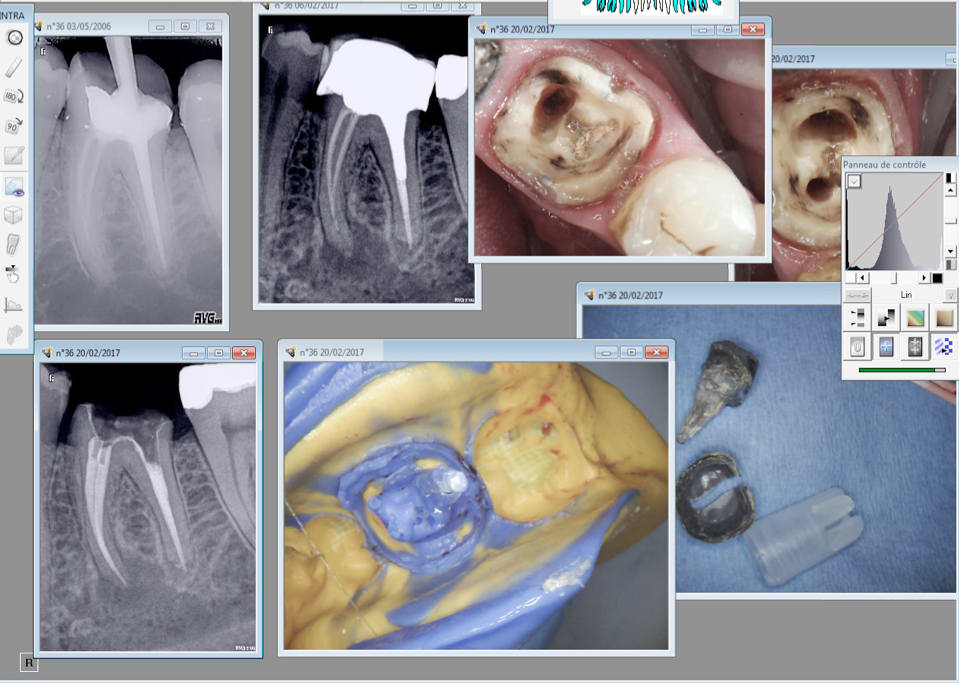

IC coiffe en 2006 sur cette 36, RTE que du distal. 2017 pÚche dans les mésiaux RTE de tous les canaux empreinte.

Je suis assez satisfait c'est propre au niveau paro, meme aprÚs séance de barbecue en 2006. -)

En 2006 avec les pro tapers c'était moyen moyen. Avec le réciproc R25 blue ca rentre comme dans du beurre. C'est pas compliqué c'est comme une bio sans l'anesthésie.

L'inlay core a dégagé en 5 secondes au coronaflex.

Ca s'appelle "fidéliser" -))))